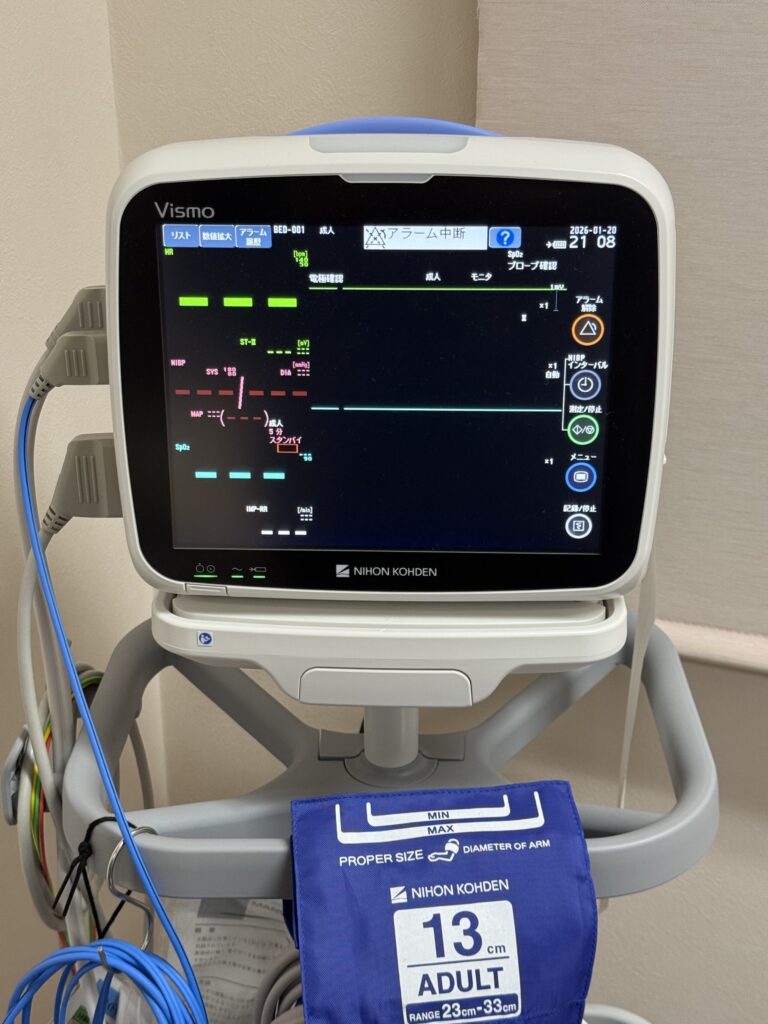

- 院内での休憩: 検査終了後、薬の効果が切れるまで1時間ほどリカバリールームでお休みいただきます。